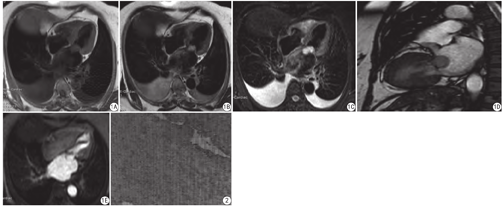

患者女,63岁,主因活动后胸闷、气短伴咳嗽2个月,加重10 d入清华大学第一附属医院。听诊:第一心音增强,各瓣膜区未及明显杂音。心电图:窦性心律,心率70次/min,AVF导联低电压,无明显ST-T改变。心脏MR平扫及增强扫描显示二尖瓣前叶左房侧附着占位病变,大小约为25 mm×13 mm×20 mm,病灶光滑,随心动周期及瓣叶运动,造成二尖瓣狭窄并中量反流,左室流出道狭窄,收缩期末内径约10 mm,病灶平扫呈等T1、长T2信号(与心肌信号比较),信号较均匀,延迟增强扫描与心血池信号一致(图1)。全麻下行二尖瓣囊肿切除术。术中所见:二尖瓣前叶左房侧可见一血性囊肿,大小为30 mm×20 mm×15 mm,与左房交通。囊液为血性。囊壁可见少量附壁血栓。病理所见:光学显微镜下观察,纤维组织囊壁多为胶原纤维,厚壁内散在少许小囊腔,腔内衬以扁平或立方细胞,囊壁内散在纤维母细胞增生,囊腔内有血栓及血块(图2)。免疫组织化学检测:CD34 (+),CD31 (+),D2-40 (-),间皮抗体(-),血内皮细胞(+),淋巴管内皮及间皮(-)。病理诊断:二尖瓣血性囊肿。

心脏血性囊肿由Elasser在1844年提出,在胎儿和儿童人群中常见,随着年龄增大而逐渐消失,故在成人群体中非常罕见[1]。血性囊肿多发生在房室间瓣膜,少数见于主动脉和肺动脉瓣[2]。目前,心脏瓣膜血性囊肿的发生最主要可能与血管内皮损伤有关[3]。其临床症状及体征不明显,因此大多数影像科医师不了解这个病变[4]。超声是诊断心脏瓣膜血性囊肿的首选方法[5],但是对于确定囊肿性质和分型有一定的难度。心血管磁共振成像(cardiovascular magnetic resonance,CMR)检查有助于了解病灶的大小、性质及周围软组织等信息。本例MRI平扫表现为:TSE T1WI呈等信号,T2WI和脂肪抑制序列呈高信号。心脏电影:在高信号的心血池衬托下呈低信号,囊肿位置和形态随心动周期没有明显改变。增强扫描:首过心肌灌注无明显强化,延迟扫描瘤体有对比剂充填与心血池信号相同。这一表现与Romano等报告的病例相符[6]。延迟增强扫描的表现与Cianciulli等[7]报道的病例表现不一致,推测本例囊肿与血管相通。鉴于此,还要与该部位好发的二尖瓣瘤、黏液瘤和乳头状纤维弹力瘤进行鉴别。二尖瓣瘤非常少见,表现为二尖瓣瓣叶突向心房的囊性病灶,但是与左心室通过瓣叶上的开口相同。因此该病变心脏电影收缩期充血扩张,舒张期排空萎缩,大小随心动周期发生变化,血性囊肿大小不随心动周期发生变化。黏液瘤有宽窄不一的蒂与二尖瓣相连,活动度大,病灶呈长或等T1、稍长T2信号,通常瘤体内信号不均匀。心脏电影显示病灶的位置形态随心动周期发生变化,增强扫描呈均匀与不均匀强化,延迟增强表现为瘤蒂和瘤壁的强化。乳头状纤维弹力瘤一般好发于主动脉瓣,其次为二尖瓣。表现为长T1、短T2信号,一般直径小于1 cm,增强扫描无强化考虑此诊断。

综上,成人二尖瓣血性囊肿临床罕见,超声定性诊断有一定难度,CMR检查有助于准确了解病灶的大小、性质及与周围组织的关系等信息。本例患者术前CMR延迟增强后见与左心房相通的囊袋状结构并与左心房的血池信号一致,其形态和位置不随心动周期变化,这一发现高度提示二尖瓣血性囊肿。